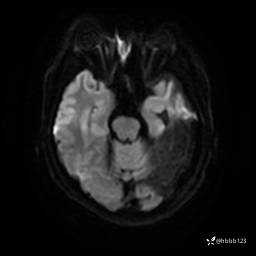

DWI: